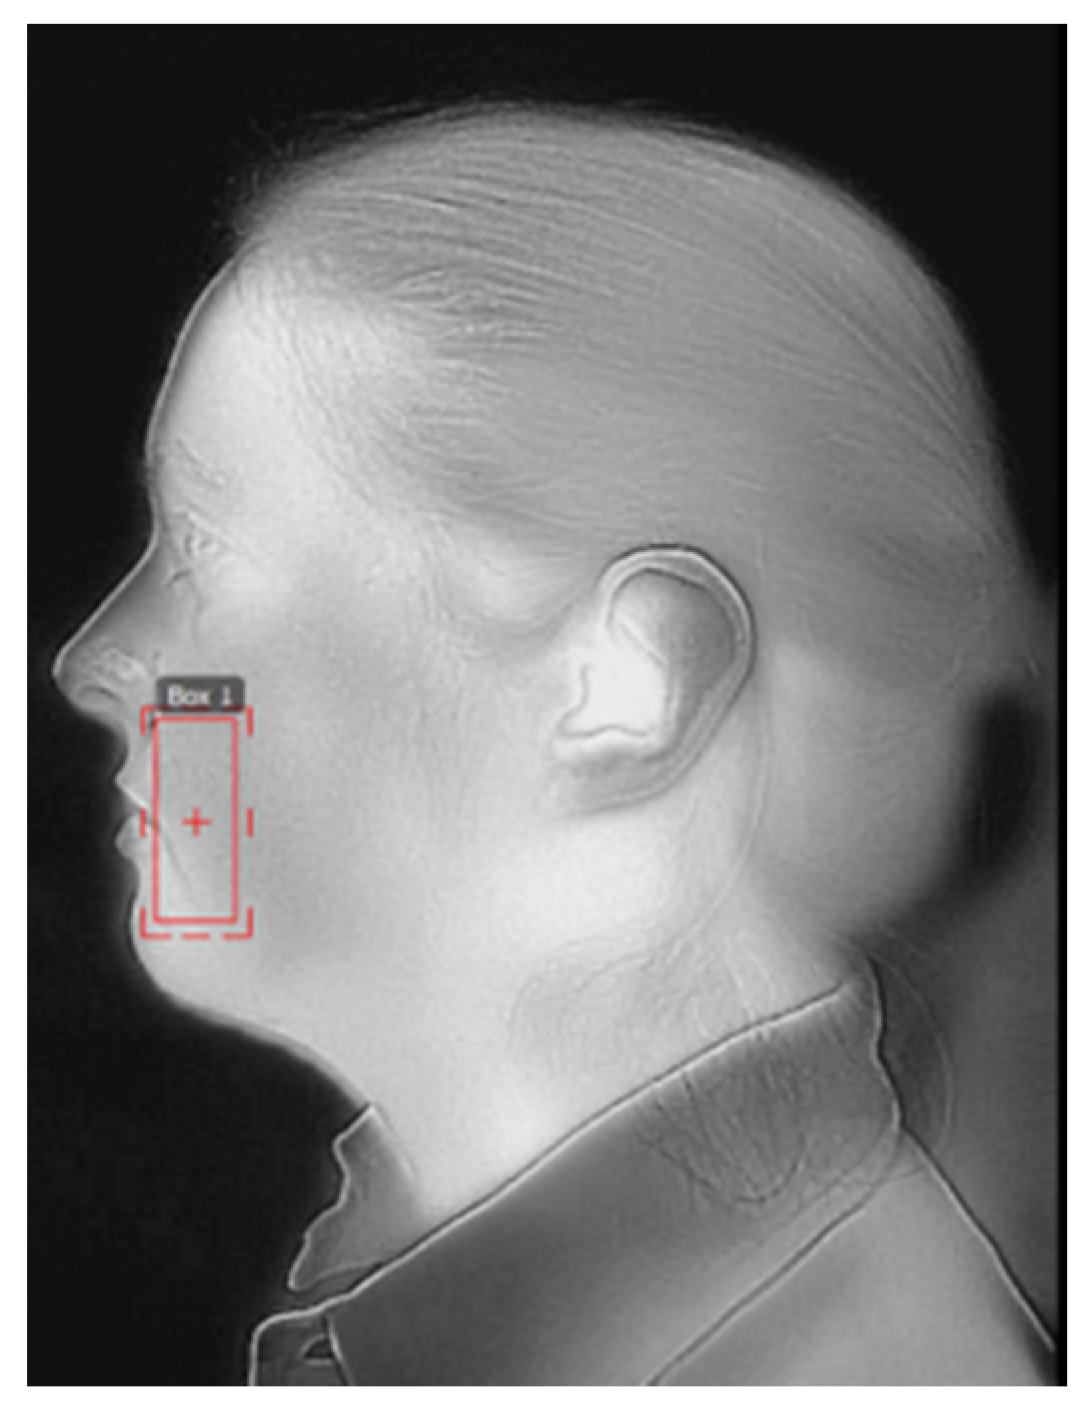

Composing the Frame

- Profile images (15 cm and 30 cm): the tip of the nose was positioned at the border of the frame with the ears maintained at the middle of the picture (Figure 4);

- Profile image (50 cm): the ears were positioned at the center of the image (Figure 5).